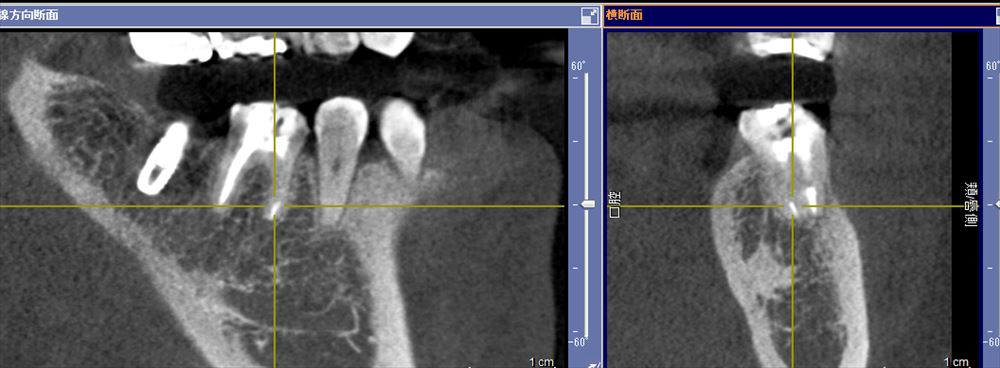

他院でリーマー破折。器具が残っています。

CTでも確認 ML根

取れました!!今日根管充填。症状もないです。

後ろのインプラントは私が去年埋入。同時に上部を作っていけそうです。歯の保存をまず考えています。